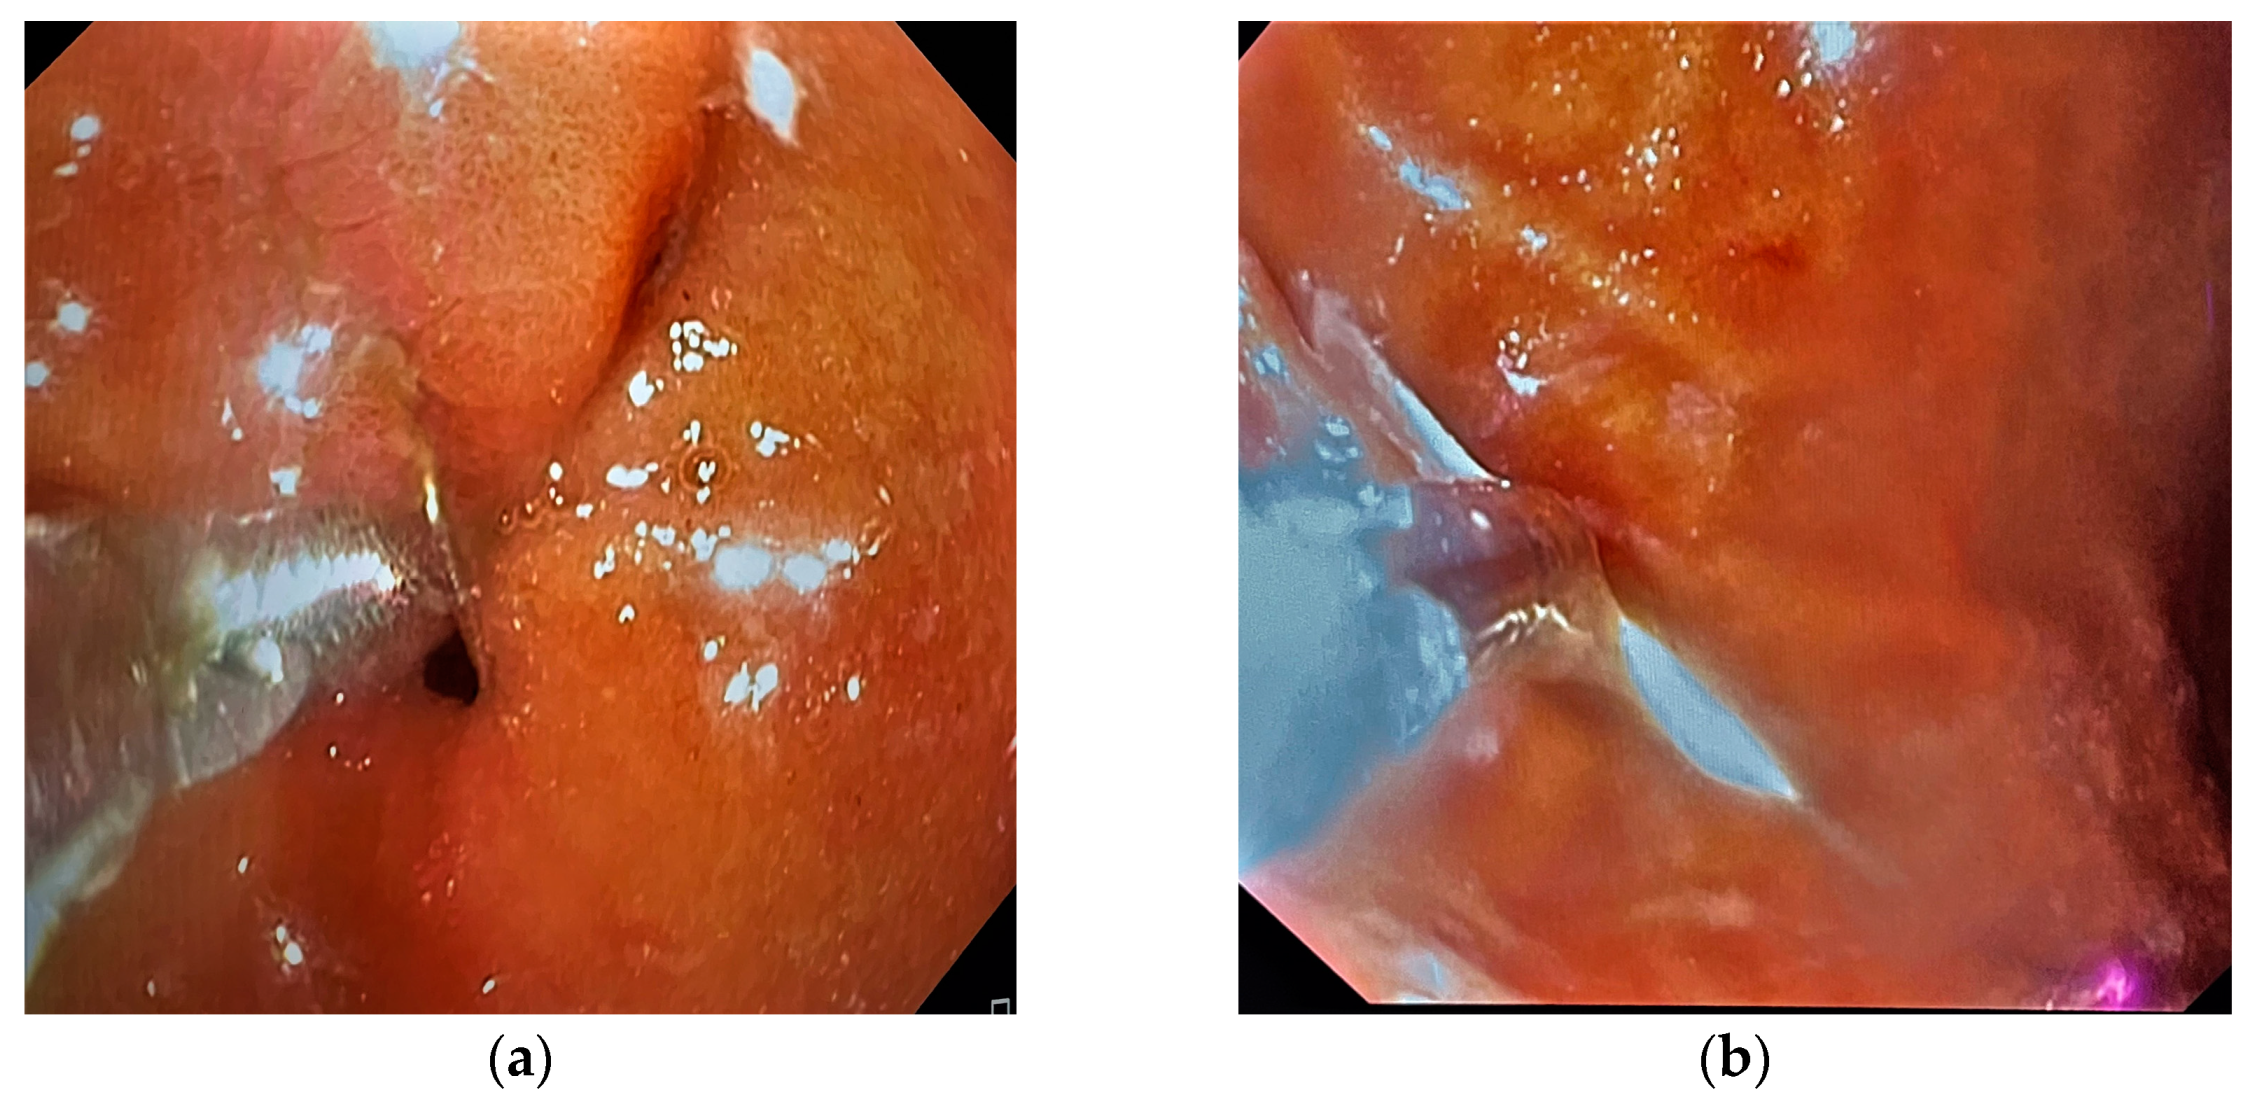

2. Case Presentation